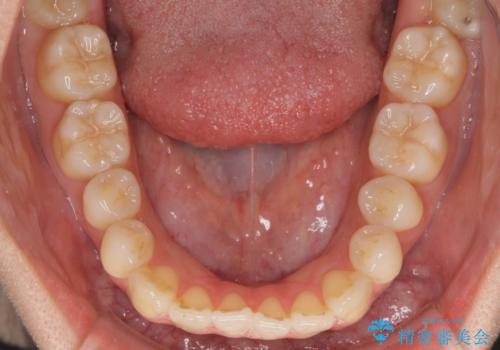

オープンバイトでかみにくい インビザラインによる矯正治療

- 前歯の上下スペースによる食べにくさを気にして来院された患者様です。

インビザラインにより上下の前歯の隙間を閉じていくこととしました。

上下の奥歯を圧下させるようにすることで、前歯を接触させるように計画しました。

上下の隙間に舌が入り込むことがオープンバイトの原因であったため、舌の筋肉のトレーニングも並行して行い、後戻りの抑制を図りました。